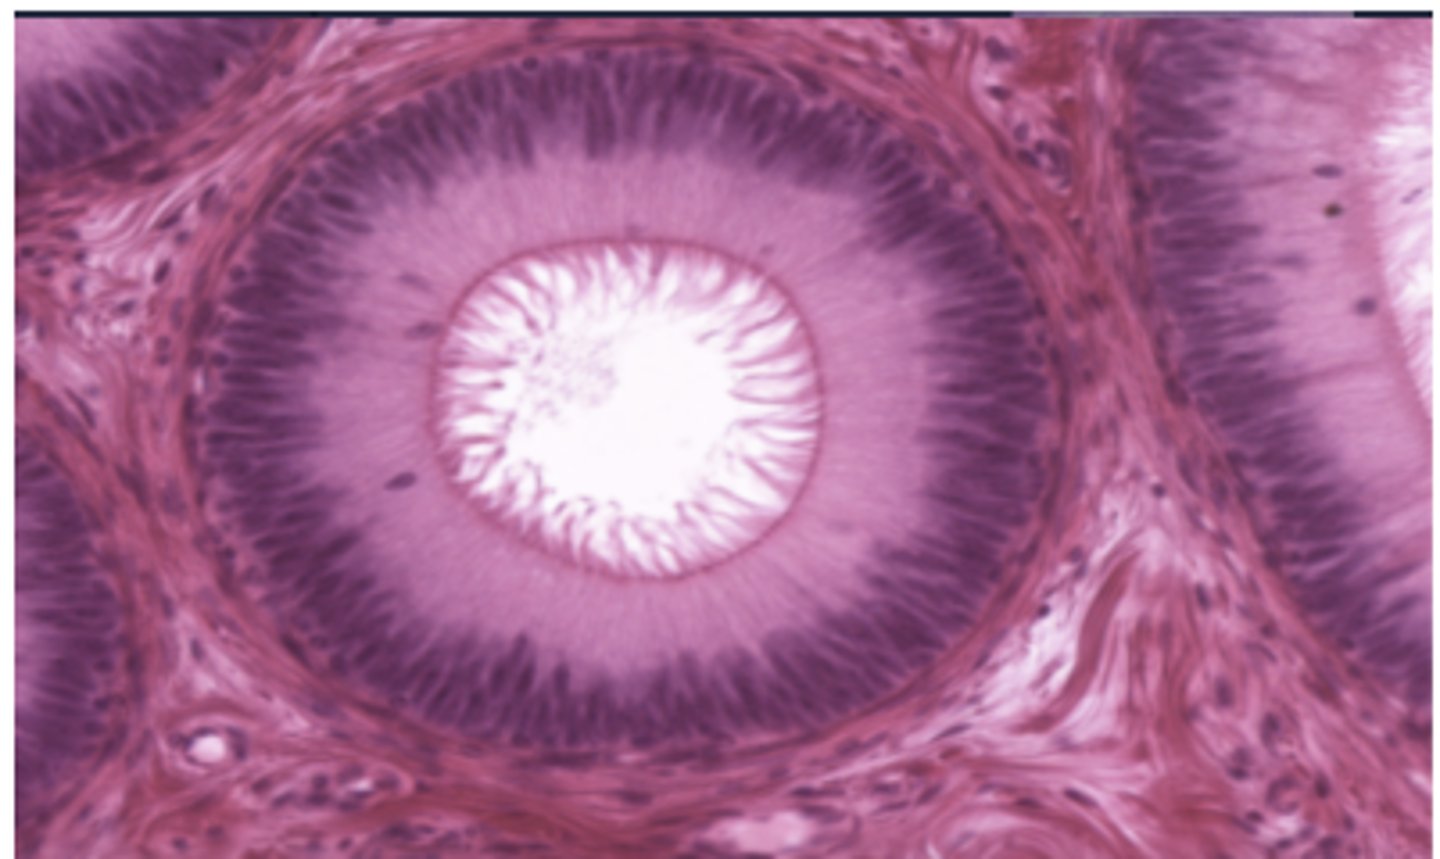

What is found in medulla of thymus

Hassall's corpuscle??